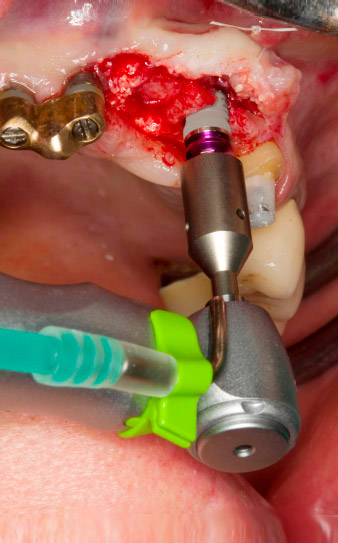

Following primary healing, the soft tissues were shaped using the basally lined bridge. Two months later the site was exposed by a slightly palatal alveolar ridge incision (Fig 2). The dimensions of the alveolar bone proved to be sufficient at position 22. Figures 2 and 4 show the preparation of the implant bed, the tapping and the implantation using Implantmed.

pilot drilling is performed with the new Implantmed and the WS-56 L contra-angle handpiece

Fig. 2: Two months later the pilot drilling is performed with the new Implantmed and the WS-56 L contra-angle handpiece (programme P1, ratio 1:1). The cooling is performed via the spray tube positioned on the left (for right-handed users).